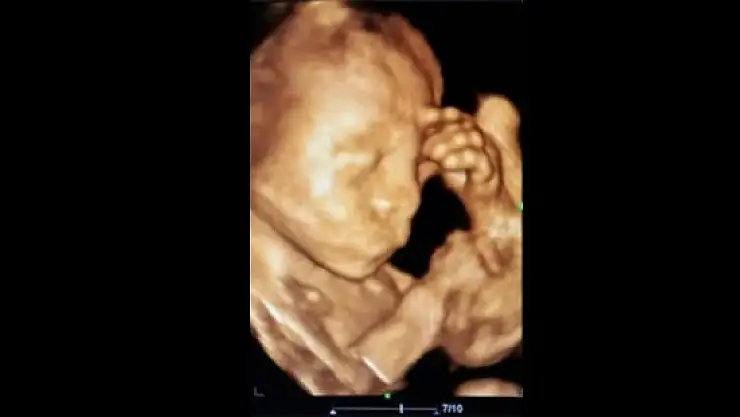

Konya’nın Ereğli ilçesinde önceki gün sosyal medyada paylaşılarak ilgi çeken, ultrasonda düşünür vaziyette görüntü veren bebeğin annesi Beyhan Öztürk, “Çocuğum doğduktan sonra havale geçirir mi diye sürekli düşünüyorum. Bebeğimin benim gibi fazla düşünmesini istemiyorum” dedi.

Ereğli’de önceki gün Kadın Hastalıkları ve Doğum Uzmanı Op. Dr. Kadriye Turgut tarafından sosyal medyada paylaşılan 23 aylık düşünen bebeğin annesi Beyhan Öztürk, bebeğinin havale geçirmesinden korktuğunu söyledi. Öztürk, doktorun kız dediği doğacak olan bebeğin beşinci çocuğu olacağını belirterek, “Dördüncü çocuğum doğduktan sonra havale geçirerek bizleri çok korkutmuştu. Ben de acaba bu çocuğum doğduktan sonra havale geçirir mi diye sürekli düşünüyorum. Doktor hanıma kontrole geldiğim zaman ultrasonda düşünüyor gibi çıkması beni sevindirdi. Bebeğimin benim gibi fazla düşünmesini de istemiyorum” dedi. Çıkan haberleri takip ettiğini de ifade eden Beyhan Öztürk, “Haberlerden sonra çok mutlu oldum. Çocuğum şu an 5 aylık ve sağlık durumu gayet iyi. Doktor hanıma da teşekkür ediyorum” şeklinde konuştu.

Op. Dr. Kadriye Turgut ise 5 aylık bebeğin sağlık durumunun gayet iyi olduğunu belirterek, “Anne gergin olduğu zaman bu gerginlik bebeğe de yansıyabilir. Bunun tıbbi bir kaynağı vardır. Anne daha önceki çocuğunun havale geçirdiğini ve bu bebeği için de endişelendiğini, bu yüzden de sürekli düşündüğünü söylüyor. Yaptığımız kontrollerde bebeğimizin hiçbir sıkıntısı görünmüyor. Ultrasonda bebeğin düşünüyor gibi oluşturduğu görüntü benim çok hoşuma gitti ve bu yüzden de sosyal medyada paylaştım” diye konuştu.